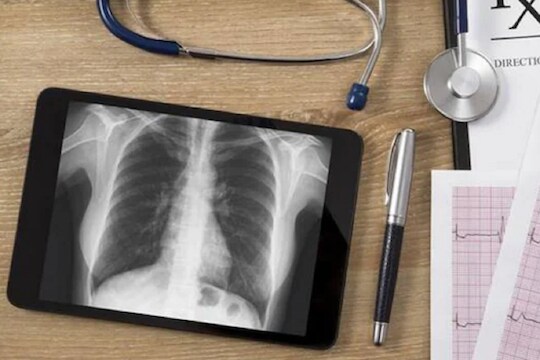

नवी दिल्ली, 8 मे : कोरोनाचा विळखा वाढत असताना, त्यावर मात करण्यासाठी अनेक टेक्नोलॉजीचाही वापर होत आहे. डिफेंस रिसर्च अँड डेव्हलपमेंट ऑर्गेनायझेशन (DRDO) आणि सेंटर फॉर आर्टिफिशियल इंटेलिजेन्स अँड रोबोटिक्सकडून (CAIR) कोरोना संक्रमित रुग्णांबाबत माहिती घेण्यासाठी एक आर्टिफिशियल इंटेलिजेन्स (AI) अल्गोरिदम डेव्हलप करण्यात आलं आहे. यात छातीच्या X-Ray द्वारे व्यक्ती कोरोना पॉझिटिव्ह आहे की नाही याबाबत माहिती मिळू शकते. या टूलच्या डेव्हलपर्सनी दिलेल्या माहितीनुसार, या टूलचं नाव Atman AI ठेवण्यात आलं आहे, ज्याचा वापर छातीच्या X-Ray स्क्रिनिंगसाठी केला जातो. यात 96.73 टक्के अचूकता असल्याचं सांगण्यात आलं आहे. CAIR, DRDO चे डायरेक्टर डॉक्टर यू. के सिंह यांनी सांगितलं, की या डायग्नोस्टिक टूलला डेव्हलप करण्याचा उद्देश फ्रंट लाईन वर्कर्स आणि संशोधकांची मदत करणं हा आहे. ज्यामुळे लवकरात लवकर Covid-19 रुग्णांबाबत माहिती मिळू शकेल आणि त्यांच्यावर लवकर उपचारही होऊ शकतील. हे टूल काही सेकंदात रेडिओलॉजिकल फाइंडिंग्सला ऑटोमेटिकली डिटेक्ट करुन Covid-19 बाबत माहिती मिळण्यास फायदेशीर ठरेल.

टेस्ट करण्याचा खर्च कमी होईल - या टूलवर काम करणाऱ्या टीमने सांगितलं, की एक्स-रे चा वापर करुन कोरोनाबाबत अधिक प्रभावीपणे माहिती घेता येईल, तसंच यासाठीचा खर्चही कमी होईल. तसंच कोरोना रुग्णांसाठी वापरण्यात येणाऱ्या CT मशीन्सवरील भार कमी होऊन, त्या इतर रुग्णांसाठी वापरल्या जातील.

हे टूल डेव्हलप करण्यासाठी RT-PCR पॉझिटिव्ह रुग्णांच्या एक्स-रे चा वापर केला गेला आहे. संक्रमित रोगाच्या वेगवेगळ्या स्टेजेसवर चाचण्या घेण्यात आल्या आहेत.